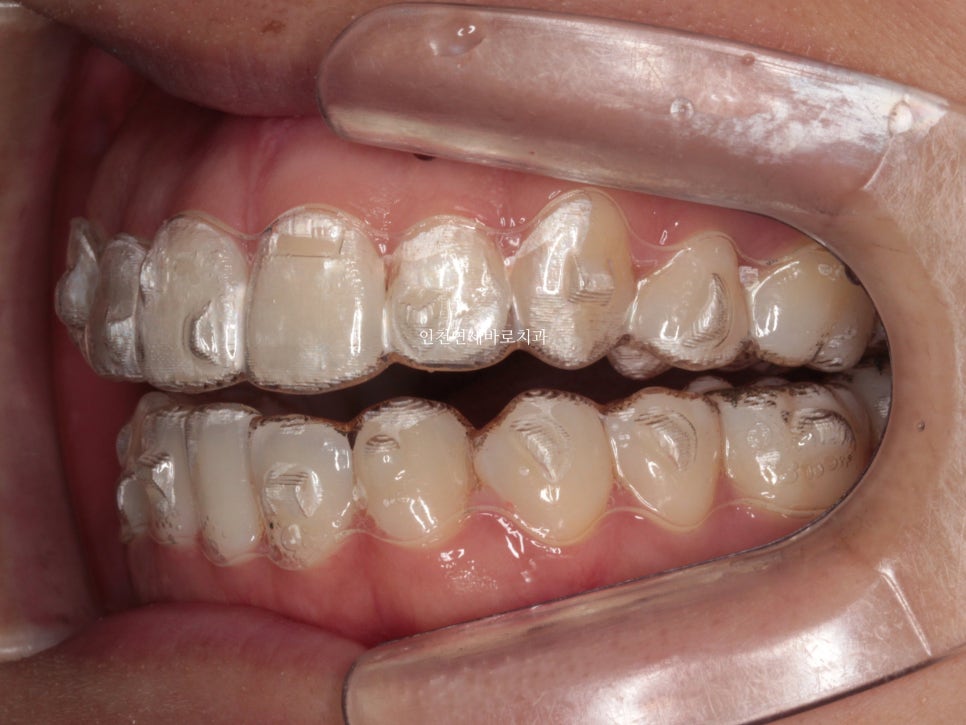

지난 주 마무리된 모습

결손치아가 있지만 교합은 문제없게 마무리

그리고 중요한 앞모습

과정이야 힘들고 오래걸리고 장치도 교체하고 어려웠지만

목표한바는 모두 달성한 치료입니다.